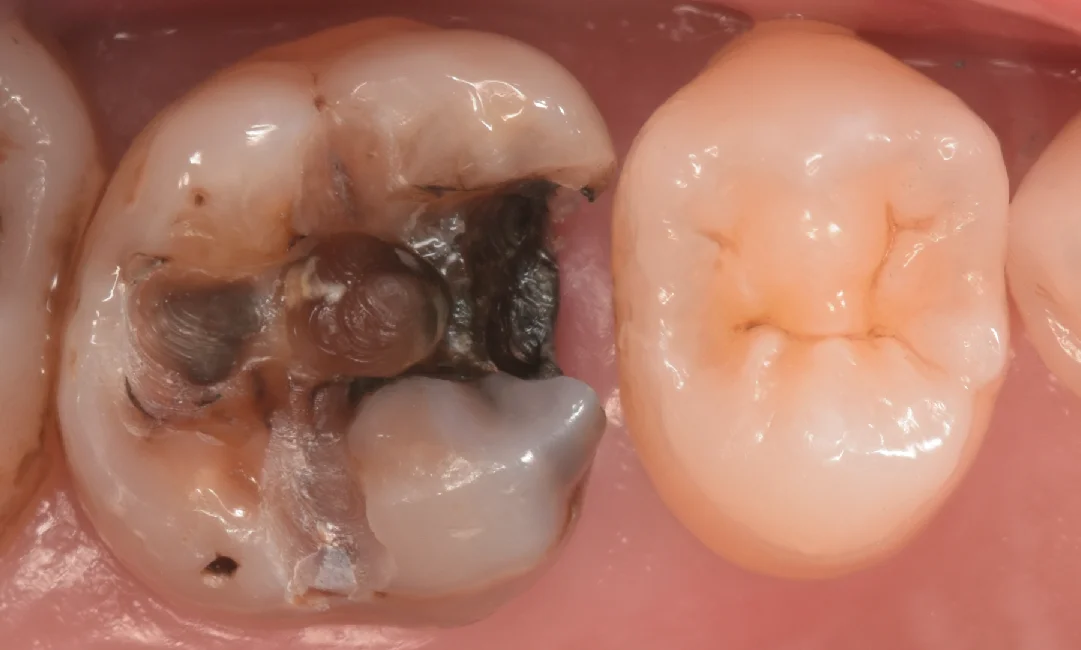

まずは術前からです。

今回は画面左側の金属部分と古い詰め物を除去してダイレクトボンディングを行なって行きます。

こちらの歯もこの先生が幼い頃に近隣の歯科医院にて治療を受けたようですね。

この金属は平成になったあたりで国内では使われなくなったと言われているアマルガムという材料になります。

通常歯科で使用する材料は硬化する際に収縮するのですが、アマルガムについては膨張するため、歯と材料の間に隙間ができづらく非常に優秀と言われたいたのですが・・・

この材料は歯と接着されているわけではないので、残っている歯に亀裂が入ったり、欠けたアマルガムから虫歯になるため実は結構予後が悪いです。

非常に小さなアマルガムであればあるいは・・・と言ったところですが、今回のように歯と隣の歯の方まで覆われている場合は非常に持たないイメージです。

今回は歯科医師という職も相まって非常に長い経過を辿りましたが・・・残念ながら限界のようですね。。。

また、アマルガムと接するようにコンポジットレジンが詰められているのですが、コンポジットレジンは金属とまともに接着できないため、その隙間から内部に細菌が侵入していると考えられます。